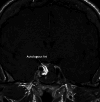

Background: Invasion of the CS is one of the limiting factors for total resection for PitNet tumors with cure rates less than 30%. Extended approaches may be considered in selective and well-studied cases of secreting adenomas.

Method: We describe the key steps of the endoscopic transcavernous approach for functional pituitary adenomas with a video illustration. The surgical anatomy is described along with the advantages and limitations of this approach.